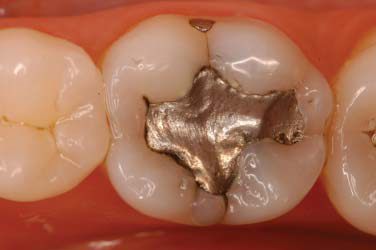

Clinical examination revealed two Class I amalgam restorations in mandibular first molar, one in the central sulcus and the other in the buccal sulcus (Figures 1 and 2). They appeared to be secondary carious lesions and were classified as clinically unsatisfactory. According to the patient, sensitivity to hot and cold had started five months before and the restoration was made 18 years earlier. There were two pigmented cracks, one on the buccal (Figures 1 and 2) and the other on the lingual surface. Occlusal contacts were checked with articulating paper and revealed a larger contact area on the occlusal surface than in other areas. Periapical and interproximal radiographs did not suggest the presence of a crack (Figure 3). Was performed tooth percussion and pulp vitality test with cold air and the patient responded with sensitivity.